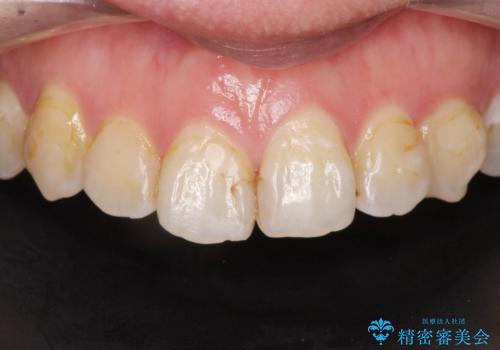

e-maxインレーによる治療

治療について

e-maxインレーは二次的にう蝕になるリスクが

銀の詰め物や樹脂の詰め物に比べて低いです。

セラミック治療の注意事項(リスク・副作用など)

- 天然歯を削ります

- 硬い素材は天然歯を傷つけてしまう場合があります

- かみ合わせや歯ぎしりが強すぎる方はセラミックが割れてしまう可能性があります